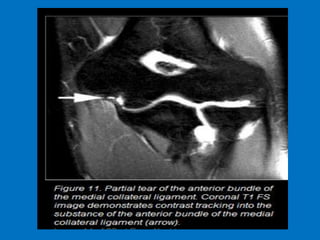

Ulnar collateral ligament (UCL) injury refers

to a sprain, partial tear or complete tear of

the ligament that traverses the inside (or

medial side) of the elbow. The UCL is the

primary stabilizer of the elbow and plays an

important role in throwing and hitting

sports, such as baseball, football and tennis.